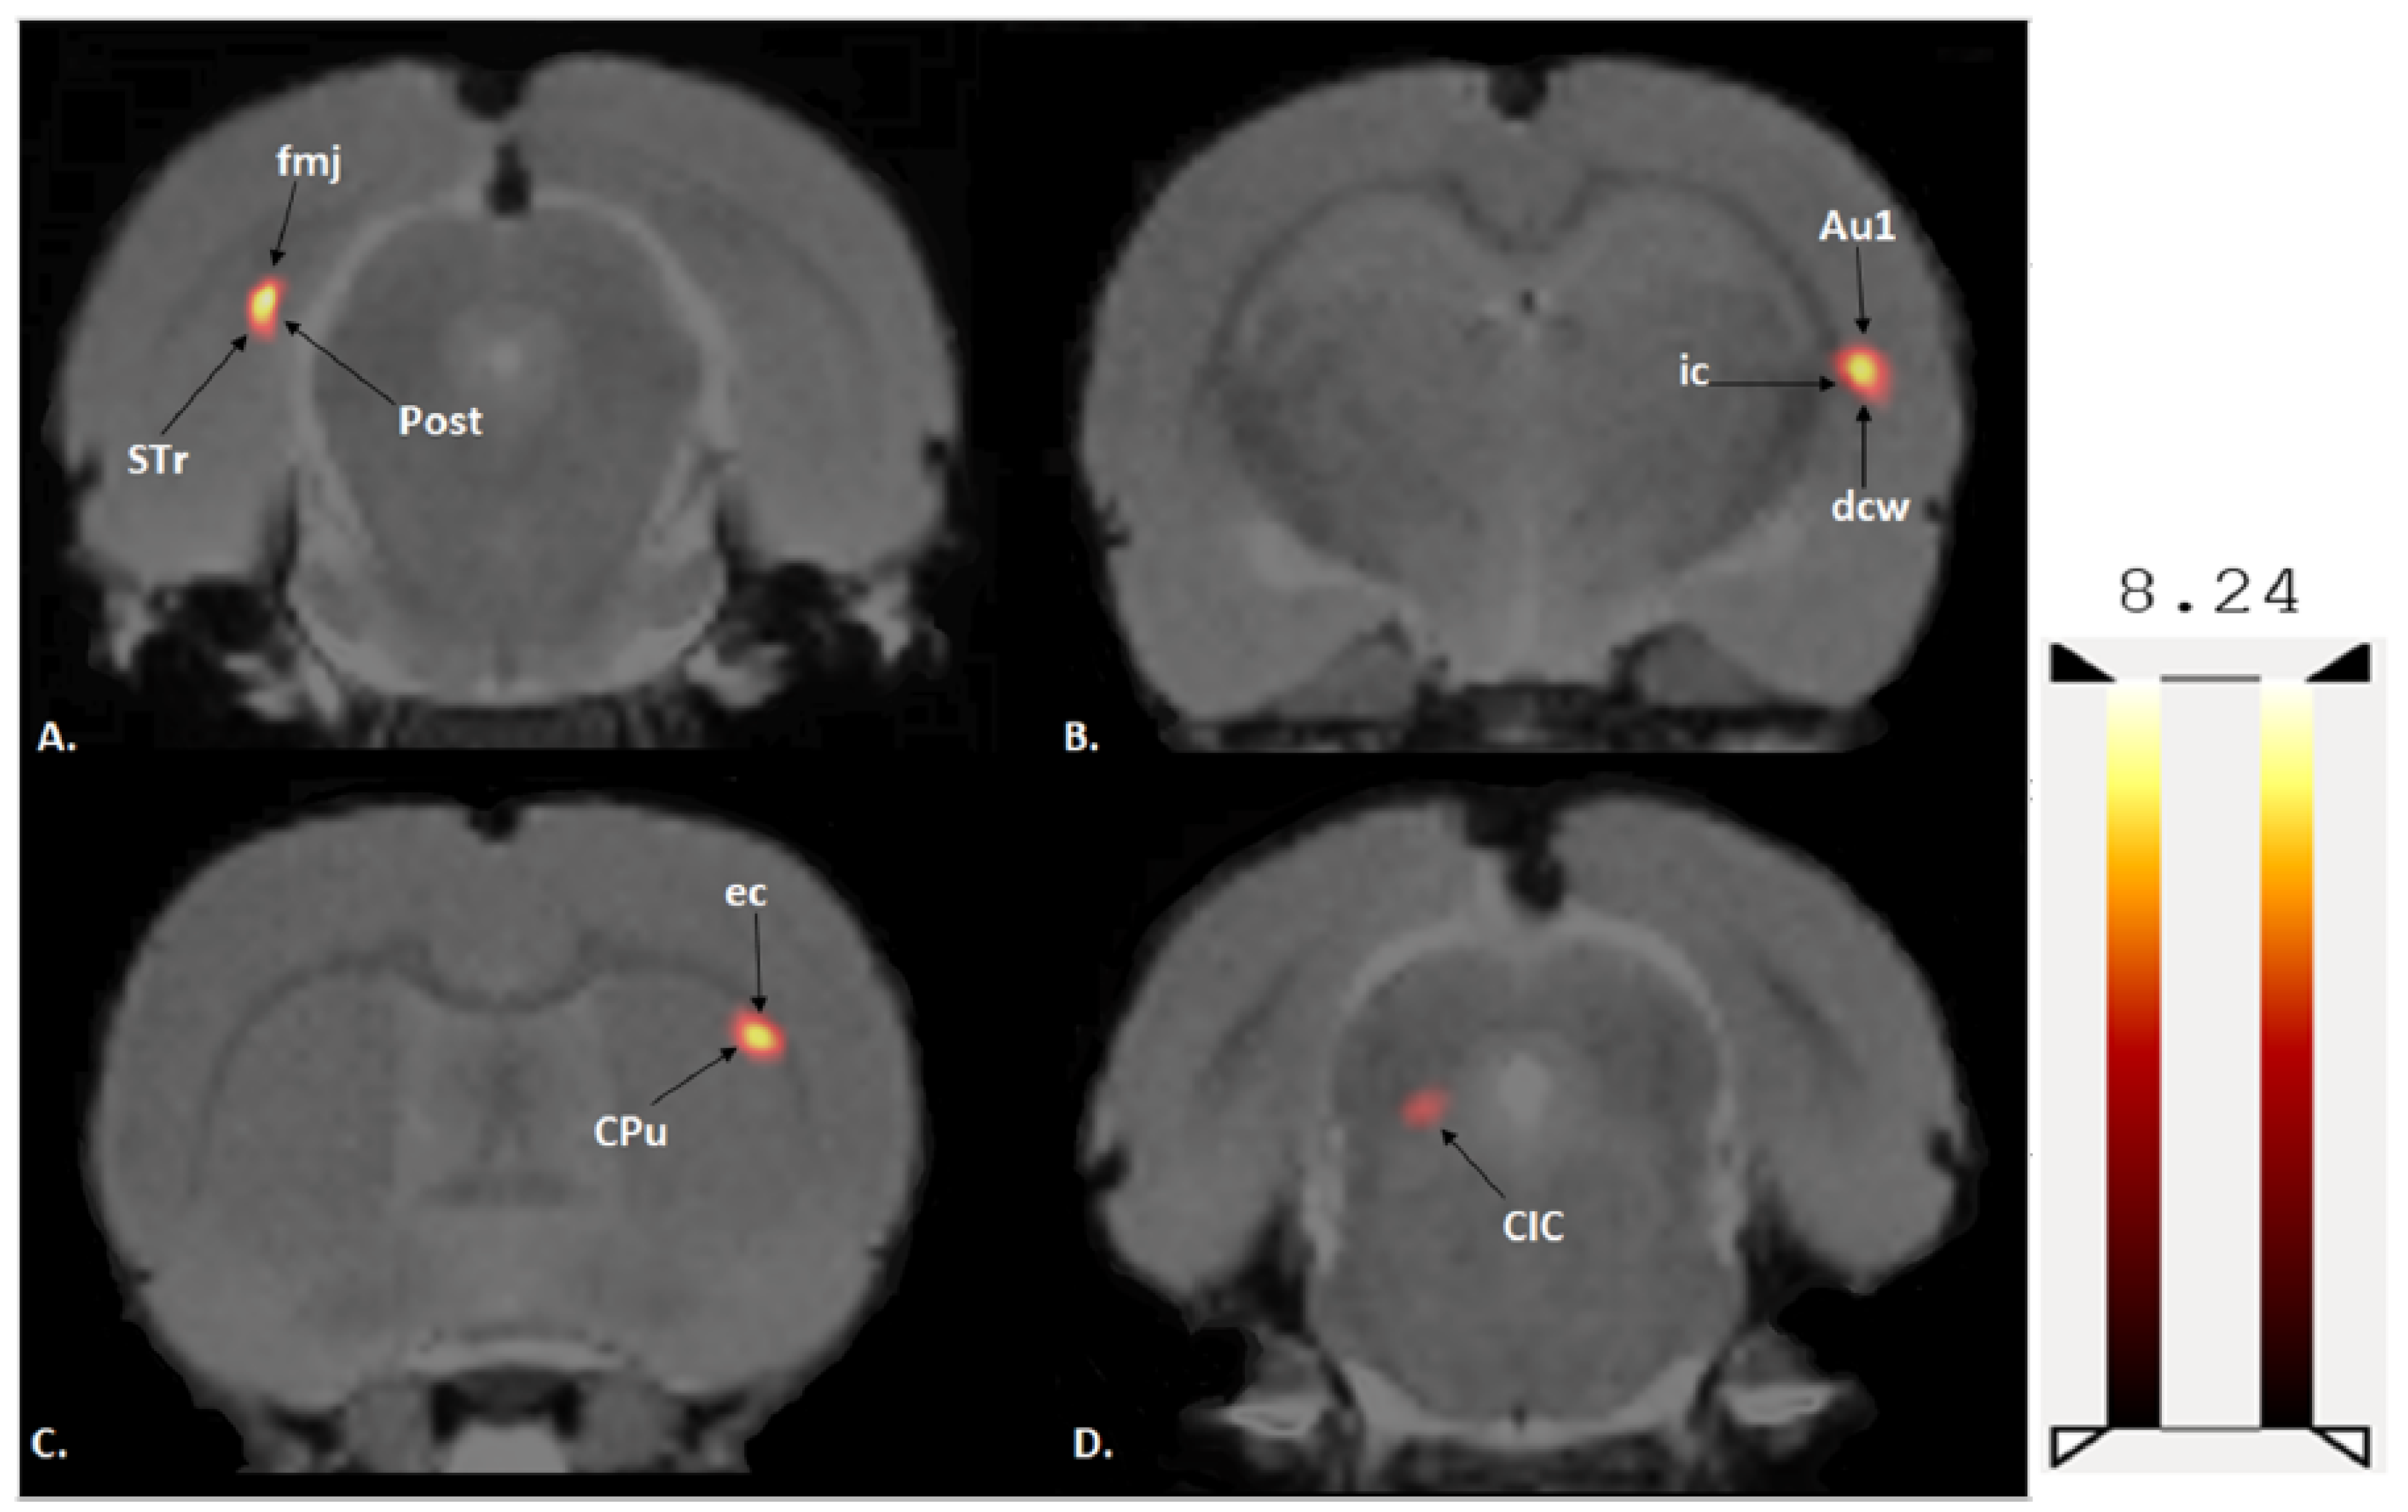

Figure 2. Examples of reconstructed PET images manually co-registered to an fMRI template. (A) PET image from an exercised rat: A1, Coronal PET image, exercised rat; A2, coronal co-registered image, exercised rat; A3, sagittal PET image, exercised rat; A4, sagittal co-registered image, exercised rat; A5, horizontal PET image, exercised rat; and A6, horizontal co-registered image, exercised rat. (B) PET images from a sedentary rat: B1, coronal PET image, sedentary rat; B2, coronal co-registered image, sedentary rat; B3, sagittal PET image, sedentary rat; B4, sagittal co-registered image, sedentary rat; B5, horizontal PET image, sedentary rat; and B6, horizontal co-registered image, sedentary rat.